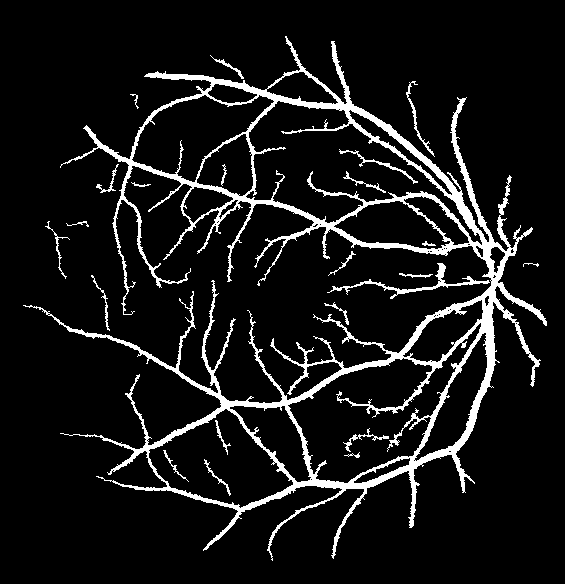

Figure 9: Ground truth (left) and segmentation result (right): (a) and (b) are the images from DRIVE dataset, (c) and (d) are the images from the STARE dataset

V-B Vessel Segmentation Performance

The segmentation performance of the proposed model on three public available datasets is given in Table IV. It can be observed that the proposed model can achieve more than 95%percent9595\% segmentation accuracy on the DRIVE, STARE and CHASE_DB1 datasets, with the highest accuracy score Acc=96.0%𝐴𝑐𝑐percent96.0Acc=96.0\% achieved in the DRIVE dataset. Some exemplary segmentation results are shown in Fig.9. When treating the unknown regions as background regions, AUC=0.833 of trimap is 2.6%percent2.62.6\% lower than the proposed model while Acc of trimap is similar to the proposed model. In addition, Se=0.679𝑆𝑒0.679Se=0.679 of trimap is 5.7%percent5.75.7\% lower than the proposed model. These observations show that trimap can already have good segmentation performance, which indicates that the selection of region features is very effective in segmenting blood vessels. From Table IV, it can be observed that the model with vessel skeleton extraction can achieve more than 5%percent55\% increase of Sensitivity𝑆𝑒𝑛𝑠𝑖𝑡𝑖𝑣𝑖𝑡𝑦Sensitivity and 2%percent22\% increase of AUC𝐴𝑈𝐶AUC compared with the model without vessel skeleton extraction while Acc𝐴𝑐𝑐Acc of the model with vessel skeleton extraction is similar to the model without vessel skeleton extraction, which demonstrates the effectiveness of vessel skeleton extraction.